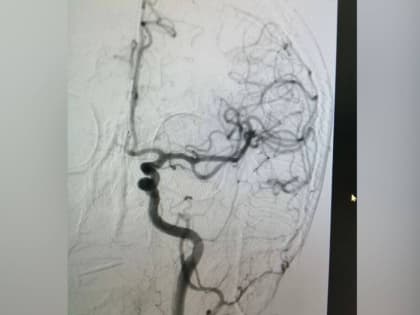

В городской больнице Орска успешно прооперировали 74-летнего мужчину с ишемическим инсультом.

При помощи современных технологий ему удалили тромб в внутримозговой артерии.

В Орске врачи городской больницы спасли 74-летнего местного жителя от ишемического инсульта.